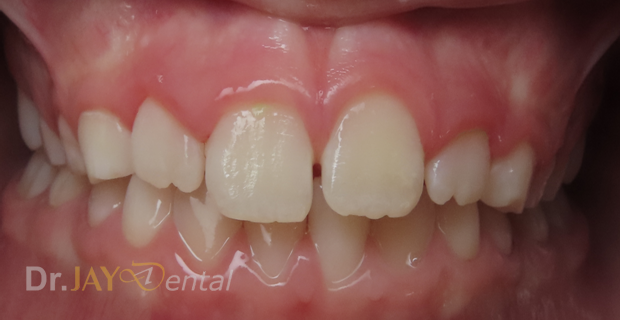

CASE 11

Lower anterior teeth crowding and the lower right canine tooth in crossbite.

Crossbite corrected and anterior crowding getting better